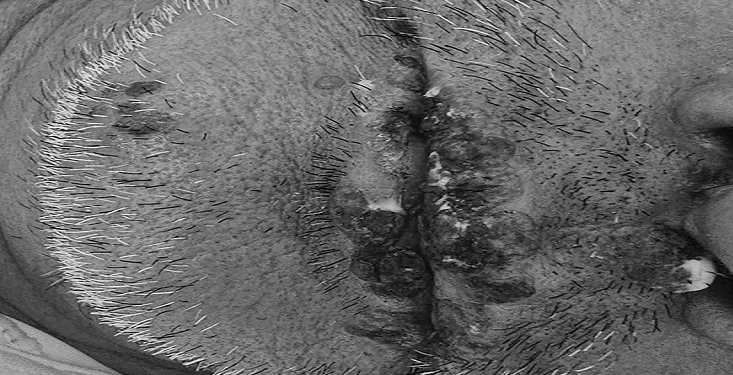

Bệnh nhân được các bác sĩ xử lý theo đúng phác đồ điều trị và được chuyển tới Bệnh viện Bệnh Nhiệt đới Trung ương để điều trị tiếp. Sau khi điều trị, tình trạng của bệnh nhân đã về bình thường. Sau đó, bệnh nhân có gặp herpes môi nguyên nhân là do suy giảm miễn dịch.